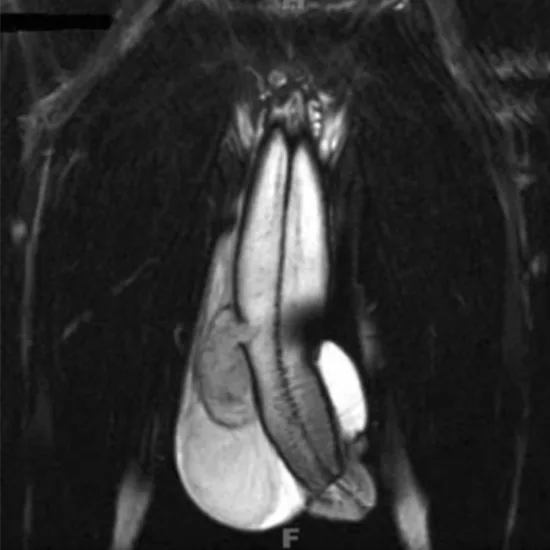

An MRI Penis Region shows the root, body, epithelium, prepuce, and surrounding soft tissues (blood vessels, lymph vessels, nerves, vas deferens).

This test is used to diagnose priapism (prolonged painful erection) and penile tumors/cysts/lumps from the penis skin.